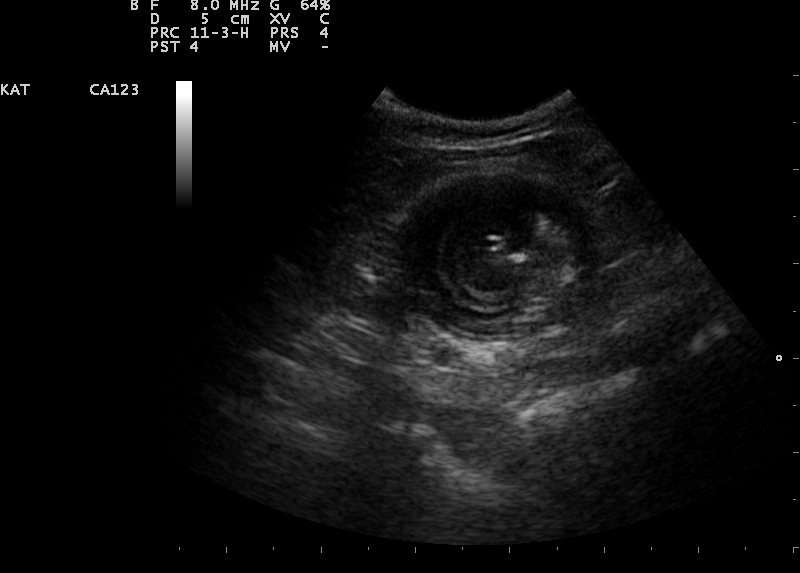

Een echo is het duidelijkst om een invaginatie te zien. Wanneer een invaginatie permanent is, zal deze met de echo meestal goed zichtbaar zijn. Echter wanneer het een temporel invaginatie is, kan dit heel lastig zijn. Een temporele invaginatie is een invaginatie die het ene moment er is en het andere moment niet. Deze invaginaties belemmeren meestal de passage maar sluiten het niet geheel af.

Een echo beeld van een darminvaginatie in dwarsdoorsnede.